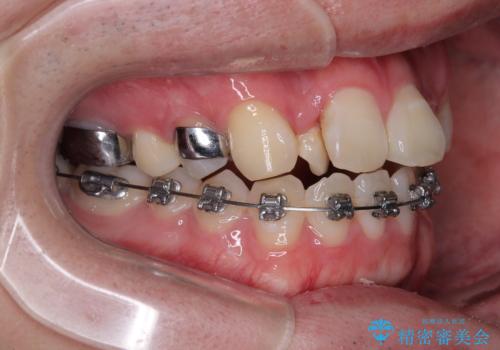

治療方針

このような歯列の狭さに起因するデコボコを改善するために、**MARPE(骨に固定する上顎急速拡大装置)**を使用して、上顎の横幅を拡大し、これにより歯が並ぶためのスペースを確保し、メタルブラケットを用いて歯列を整えていく計画としました。

費用面を考慮し、装置はコストパフォーマンスに優れたメタルブラケットを選択。見た目よりも機能と効果を重視したい方には特におすすめの選択肢です。